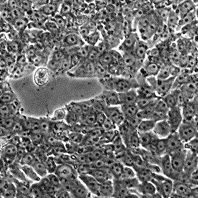

Происхождение: человек, аденокарцинома прямой кишки.

Морфология: эпителиоподобная

Способ культивирования: монослойный